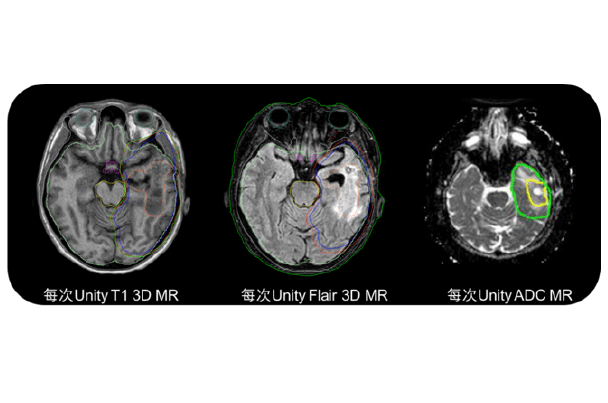

磁共振脑组织成像比传统X线或CT成像模式相比,肿瘤自身和周围健康脑组织成像分辨更高,多模态成像结合让靶区勾画更加精准,投照更加精确,对健康脑组织保护更加。治疗过程中可针对肿瘤变化,采用不同的扫描序列成像知道自适应治疗方案调整。未来的磁共振功能成像技术也为后续治疗方案的设定提供指导依据。